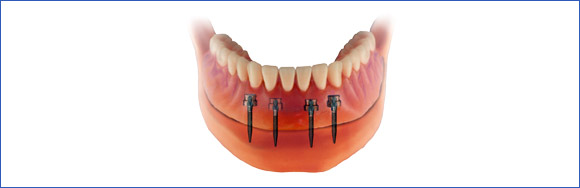

c) Prothesenstabilisierung durch Mini-Implantate

a) Umfangreiche Versorgung mit einem herausnehmbaren Zahnersatz

Versorgung vom zahnlosen Kiefer: